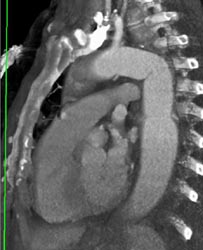

Diagnosis

Post Arch Repair